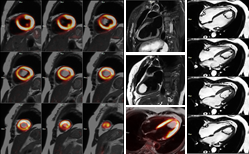

PET/MR是目前世界上最先進(jìn)的分子影像學(xué)檢查設(shè)備,它把正電子發(fā)射計(jì)算機(jī)斷層掃描儀(PET)與磁共振成像系統(tǒng)(MR)有機(jī)的整合,從而實(shí)現(xiàn)一次掃描同時(shí)獲得兩種模態(tài)的數(shù)據(jù),既結(jié)合了MR系統(tǒng)的軟組織高分辨力多參數(shù)多功能成像特性,又結(jié)合了PET系統(tǒng)的放射性示蹤劑高靈敏度以及數(shù)據(jù)半定量化特性,實(shí)現(xiàn)在分子水平對(duì)疾病進(jìn)行功能代謝及形態(tài)結(jié)構(gòu)的成像檢查,診斷效能明顯提高。PET/MR優(yōu)質(zhì)的成像技術(shù)與豐富的后處理應(yīng)用相結(jié)合,為臨床研究探索提供更多可能,是高端醫(yī)學(xué)影像診斷設(shè)備領(lǐng)域最尖端技術(shù)的代表。PET/MR作為高端醫(yī)學(xué)影像診斷設(shè)備領(lǐng)域最尖端技術(shù)的代表,被譽(yù)為“科技皇冠上的明珠”,其多 模態(tài)、多參數(shù)成像,對(duì)帕金森、老年癡呆等神經(jīng)退行性疾病與肝癌、胰腺癌、癲癇、多發(fā)性骨髓瘤等復(fù)雜疾病精準(zhǔn)診斷及研究有重要意義。

PET/MR在顱腦腫瘤、神經(jīng)內(nèi)分泌腫瘤、胰腺癌、前列腺癌、乳腺癌、肝癌、宮頸癌、頭頸部腫瘤、多發(fā)性骨髓瘤、淋巴瘤、宮頸癌等腫瘤疾病診斷方面具有顯著優(yōu)勢(shì)。 在腫瘤的診斷、TNM臨床分期、治療后再分期,腫瘤治療療效評(píng)價(jià)和監(jiān)測(cè),良、惡性疾病的鑒別診斷,引導(dǎo)腫瘤穿刺活檢,腫瘤放療靶區(qū)勾畫(huà),不明原因發(fā)熱、腫瘤標(biāo)志物升高、副癌綜合征等疑難病癥的診斷,腫瘤高危因素患者的腫瘤篩查等方面發(fā)揮重要的作用。

對(duì)于神經(jīng)系統(tǒng)疾病,PET與MR圖像提供了關(guān)于大腦解剖、生理、代謝與功能方面的信息。PET/MR可實(shí)現(xiàn)對(duì)腦神經(jīng)系統(tǒng)更精準(zhǔn)的定位與定量,從分子水平上來(lái)揭示人腦生理、病理變化,在腦腫瘤、神經(jīng)退行性疾病、癲癇等疾病的診斷與治療中可發(fā)揮重要的作用。

在心血管疾病診斷方面,PET/MR通過(guò)多參數(shù)、多平面和多序列成像可清晰顯示解剖結(jié)構(gòu)、運(yùn)動(dòng)功能、血流灌注和組織特性,通過(guò)MR序列對(duì)PET圖像進(jìn)行呼吸運(yùn)動(dòng)校正,實(shí)現(xiàn)時(shí)間和空間上最佳配準(zhǔn)的一站式評(píng)估,對(duì)心血管疾病的診斷與治療具有重要的意義。PET/MR可以進(jìn)行心肌灌注及心肌活力評(píng)價(jià)、風(fēng)險(xiǎn)分層、預(yù)后、指導(dǎo)治療,心臟動(dòng)脈硬化斑塊成像,評(píng)價(jià)瘢痕范圍(LGE)、左室功能,評(píng)價(jià)炎性心肌病及浸潤(rùn)性心肌病的活動(dòng)狀態(tài),心肌淀粉樣變的評(píng)價(jià)